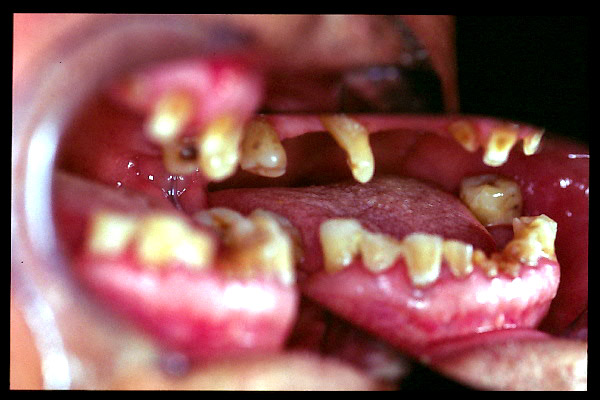

CM Caries y enfermedad periodontal avanzada